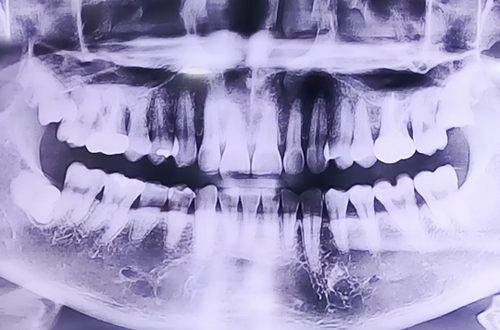

BEFORE

왼쪽 위 어금니 쪽에 극심한 통증을 호소하신 환자분이십니다.

X-ray 상에서는 치아에 큰 이상이 없어 보였지만 치아를 자세히 검사해 보니 왼쪽 위 어금니가 반으로 쪼개진 상태로 발치 이후 즉시 임플란트 치료를 진행하였고 뼈가 비어있는 부분들은 임플란트 주변 뼈이식을 진행해 드리면서 마무리해드렸습니다.